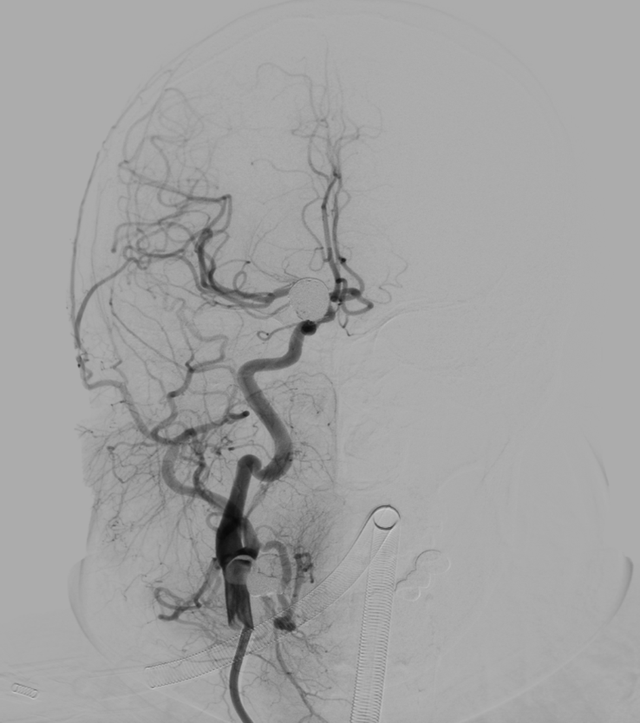

3月4日下午,仇汉诚博士达到医院后,立即赶往复合手术室着手准备手术。14点手术正式开始。仇汉诚博士带领神经外科主任张卫东、昝春树医生团队,通过三D旋转造影选择最佳工作角度,经过塑形后的微导管将弹簧圈顺利送进动脉瘤腔。首枚弹簧圈成篮稳定,半释放支架后继续填塞弹簧圈。5枚弹簧圈置放后,动脉瘤致密填塞。即刻造影显示:支架完全释放后,打开良好,完全覆盖瘤颈,动脉瘤囊内血流消失。手术历经2小时,顺利完成。术后,患者各项生命指征良好,恢复良好,2天后便完全康复返回工作岗位。

神经介入治疗,不用开刀,只需通过导管和导丝,在DSA造影下,从股动脉血管向上,沿着血管“山路十八弯”到达患处,将导丝推入“填”满气球,让血液逐渐在此次形成血栓,让气球不再增大,从而避免血管破裂发生。